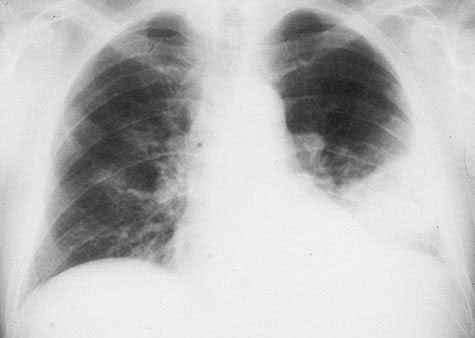

Chest x-ray is obtained and is shown.

Which of the following is the correct interpretation of the chest x-ray? (Please select only one option.)